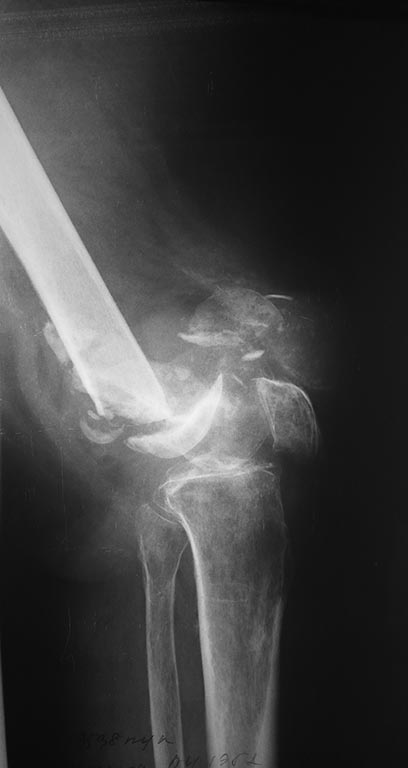

[Ortho] Перелом дистального отдела бедра

Перелом бедра у женщины 65 лет, случился 7 мес. назад( падение с высоты

роста на колено) . Живет в деревне, лечил хирург, снимки ни разу не делали.

Со слов больной после травмы в области коленного сустава была рана,

долго заживала.

Пациентка весит 120кг. В настоящее время передвигается в кресле коляске,

правая нога не опорная.Снимки и внешний вид конечности прилагаются

(свежие и единственные).

Из сопутствующей патологии: ожирение 3ст, артериальная гипертензия и

сахарный диабет 2тип, компенсация. Пациентка очень хочет самостоятельно

передвигаться.

Планируем выполнить артродез коленного сустава длинным штифтом(

бедро-голень). Хотелось услышать ваше предложения и мнения по тактике,

возможные варианты оперативного лечения.